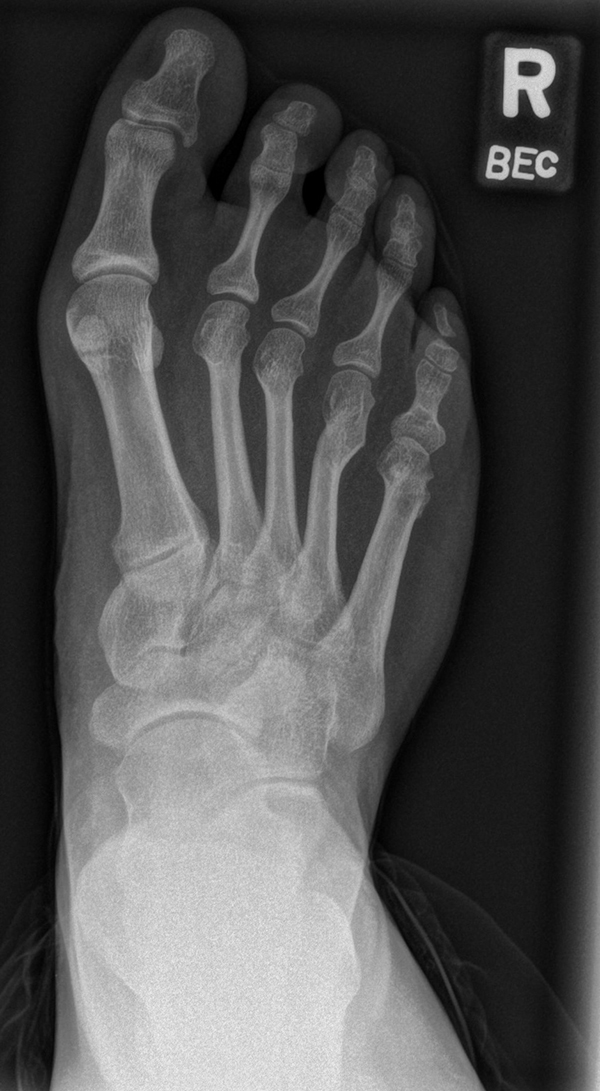

In der Regel bestehen aktive Wachstumsfugen bei Mädchen bis zum 12. und bei Jungen bis zum 14. Lebensjahr, mit Abweichungen von einem Jahr nach unten und nach oben. Präzise Informationen unter anderem darüber gibt das präoperative Röntgenbild (Abb. 2).

Abb. 2 a-c: offene Wachstumsfugen MT I Basis und Zehen (a), teilweise geöffnete Wachstumsfugen (b) und geschlossene Wachstumsfugen (c).